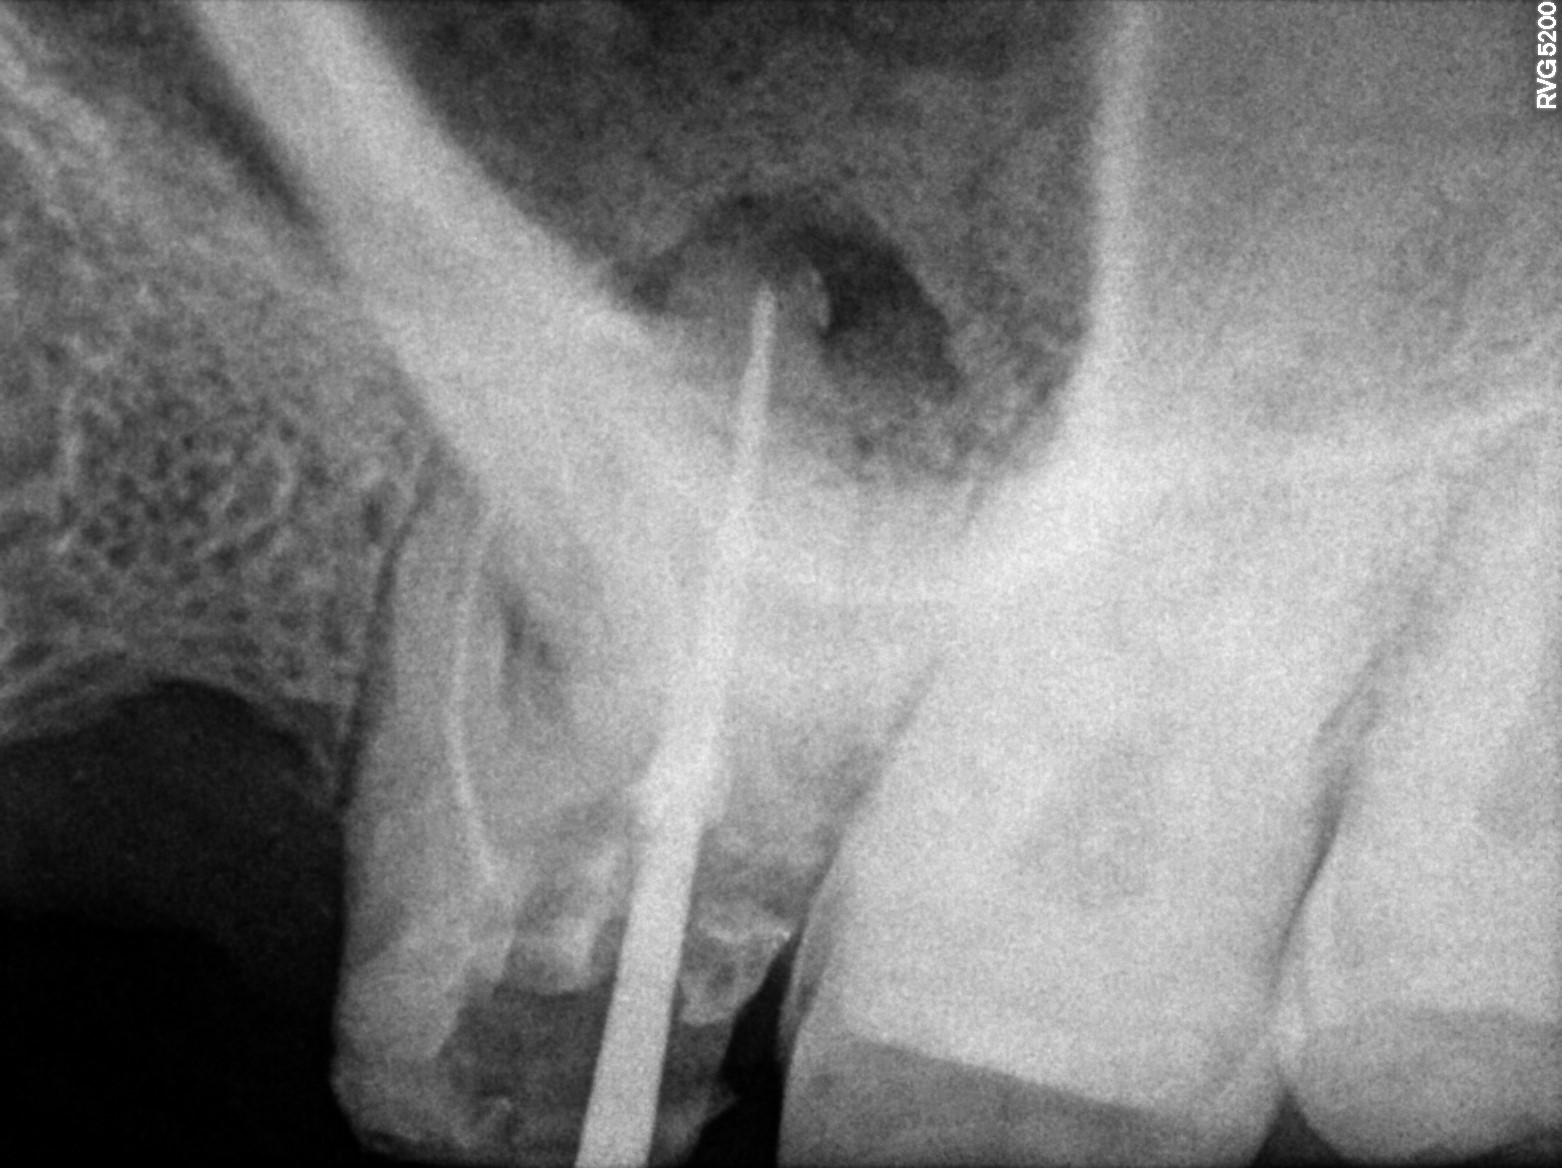

Dental Radiographs FHIR: DocumentReference · LOINC 24641-7

2 (2).jpg

24641-7